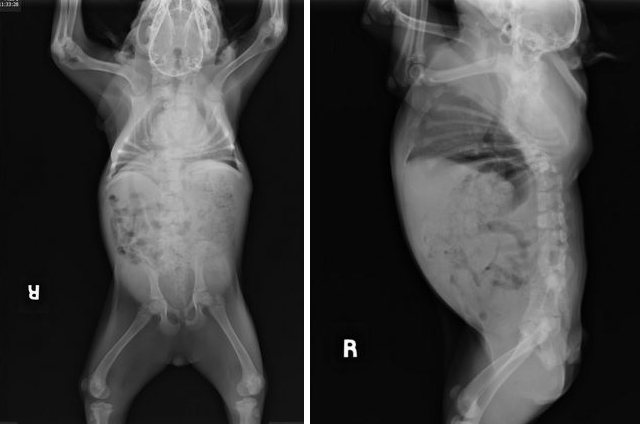

A esta preciosa perrita le falta un trozo de columna vertebral por lo que sus órganos están comprimidos en menos espacio que un perro sin su problema. Además, su constitución no es exactamente igual que la del resto de sus congéneres. Cuando la mujer que la recogió se dio cuenta de la situación, acudió al veterinario para sacrificarla. Allí apareció en ángel de la guarda de PIG: Kim Dillenbeck. Cuando la vio se enamoró de ella y se informó sobre su estado. Le dijeron que tenía el tronco muy corto y que los órganos vitales estaban comprimidos en el abdomen por lo que su aspecto es abultado. De hecho, le llaman la perra acordeón por su gracioso aspecto. También dicen que se parece a un cerdito por lo que su nueva mamá la bautizó como PIG cuando la adoptó las pasadas navidades.

pig_6PIG tiene ahora 8 meses y pesa 6,8 kilos mientras que sus hermanas alcanzan ya casi los 20 kilos. El problema es que, si sigue aumentando de peso y sube otros 10 kilos, su vida estaría en peligro. Los órganos crecerían más que su cuerpo y no podría soportarlo. De ahí la importancia de vigilarla de cerca y de intentar que esto no suceda.